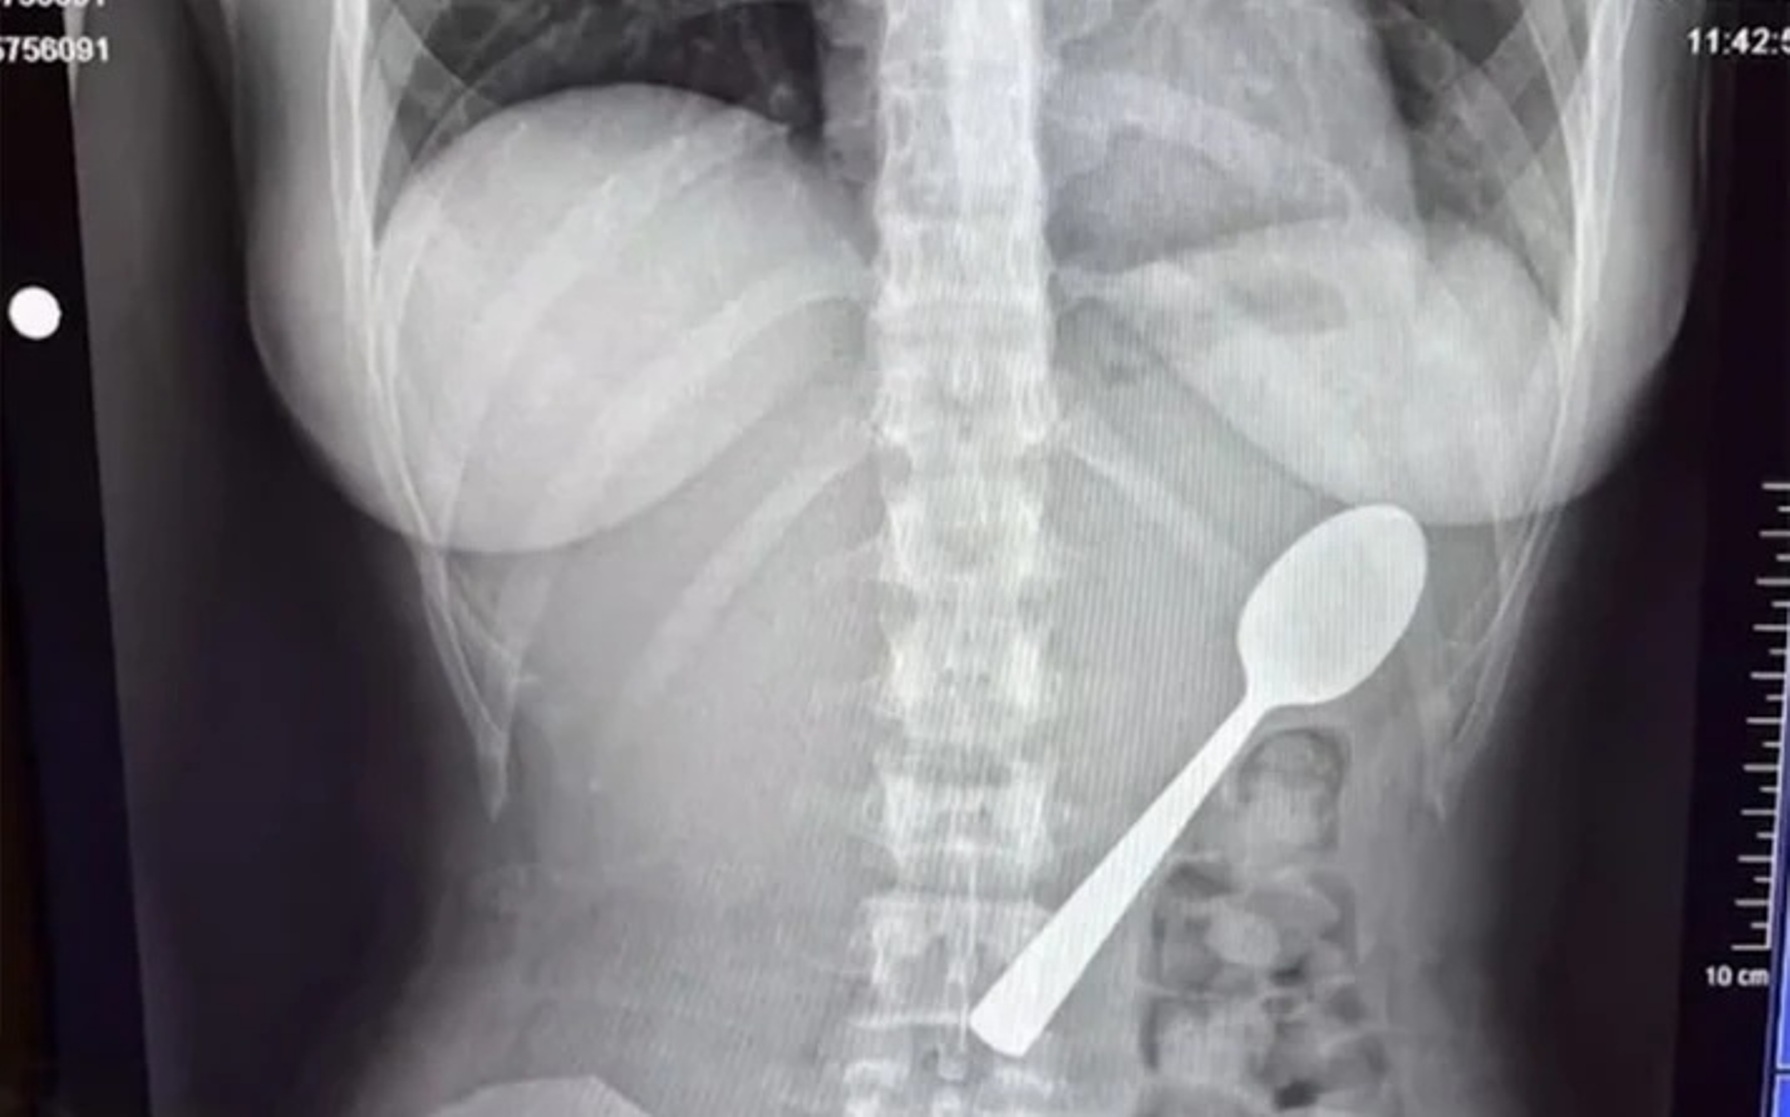

Δεν πίστευαν αυτό που «βρήκαν» γιατροί στο Βέλγιο

Γυναίκα κατάπιε κουτάλι 17 εκατοστών